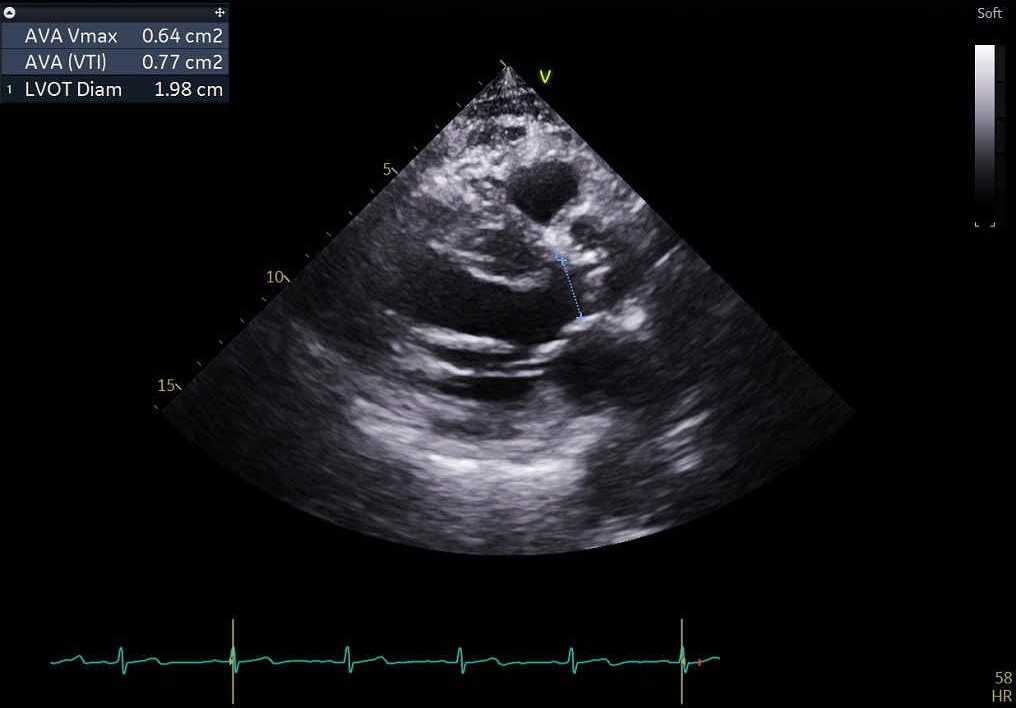

The echocardiographic findings indicate an LVEF of 55%, an aortic valve area of 0.77 cm², a maximum velocity of 3.28 m/s, a mean pressure gradient of 22 mmHg. Intermittent shortness of breath and heart failure symptoms have been reported for more than six months and are deemed to be related to low flow, low gradient severe aortic stenosis. His surgical risk, represented by an STS score of 12.4%, reinforces the decision to proceed with the TAVI intervention.